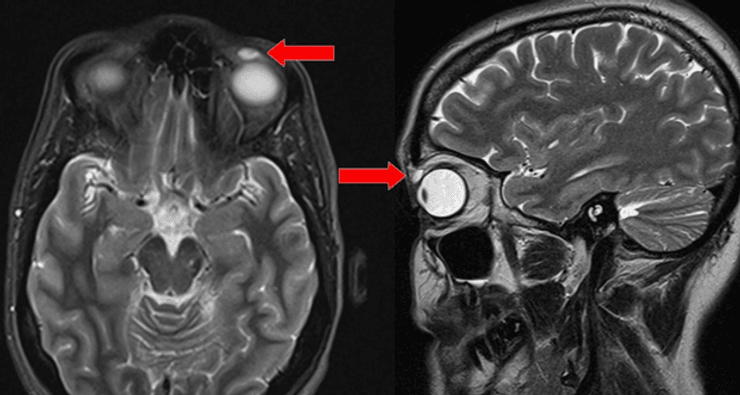

Сначала специалисты провели сканирование с помощью МРТ и обнаружили образование величиной в шесть миллиметров. Веко не показывало никаких признаков травмы, однако, когда опухоль надрезали, внутри обнаружили жесткую контактную линзу. При ее удалении возникли осложнения, потому что структура объекта стала хрупкой и врачи боялись оставить внутри осколки.

Фото: BMJ Case Reports